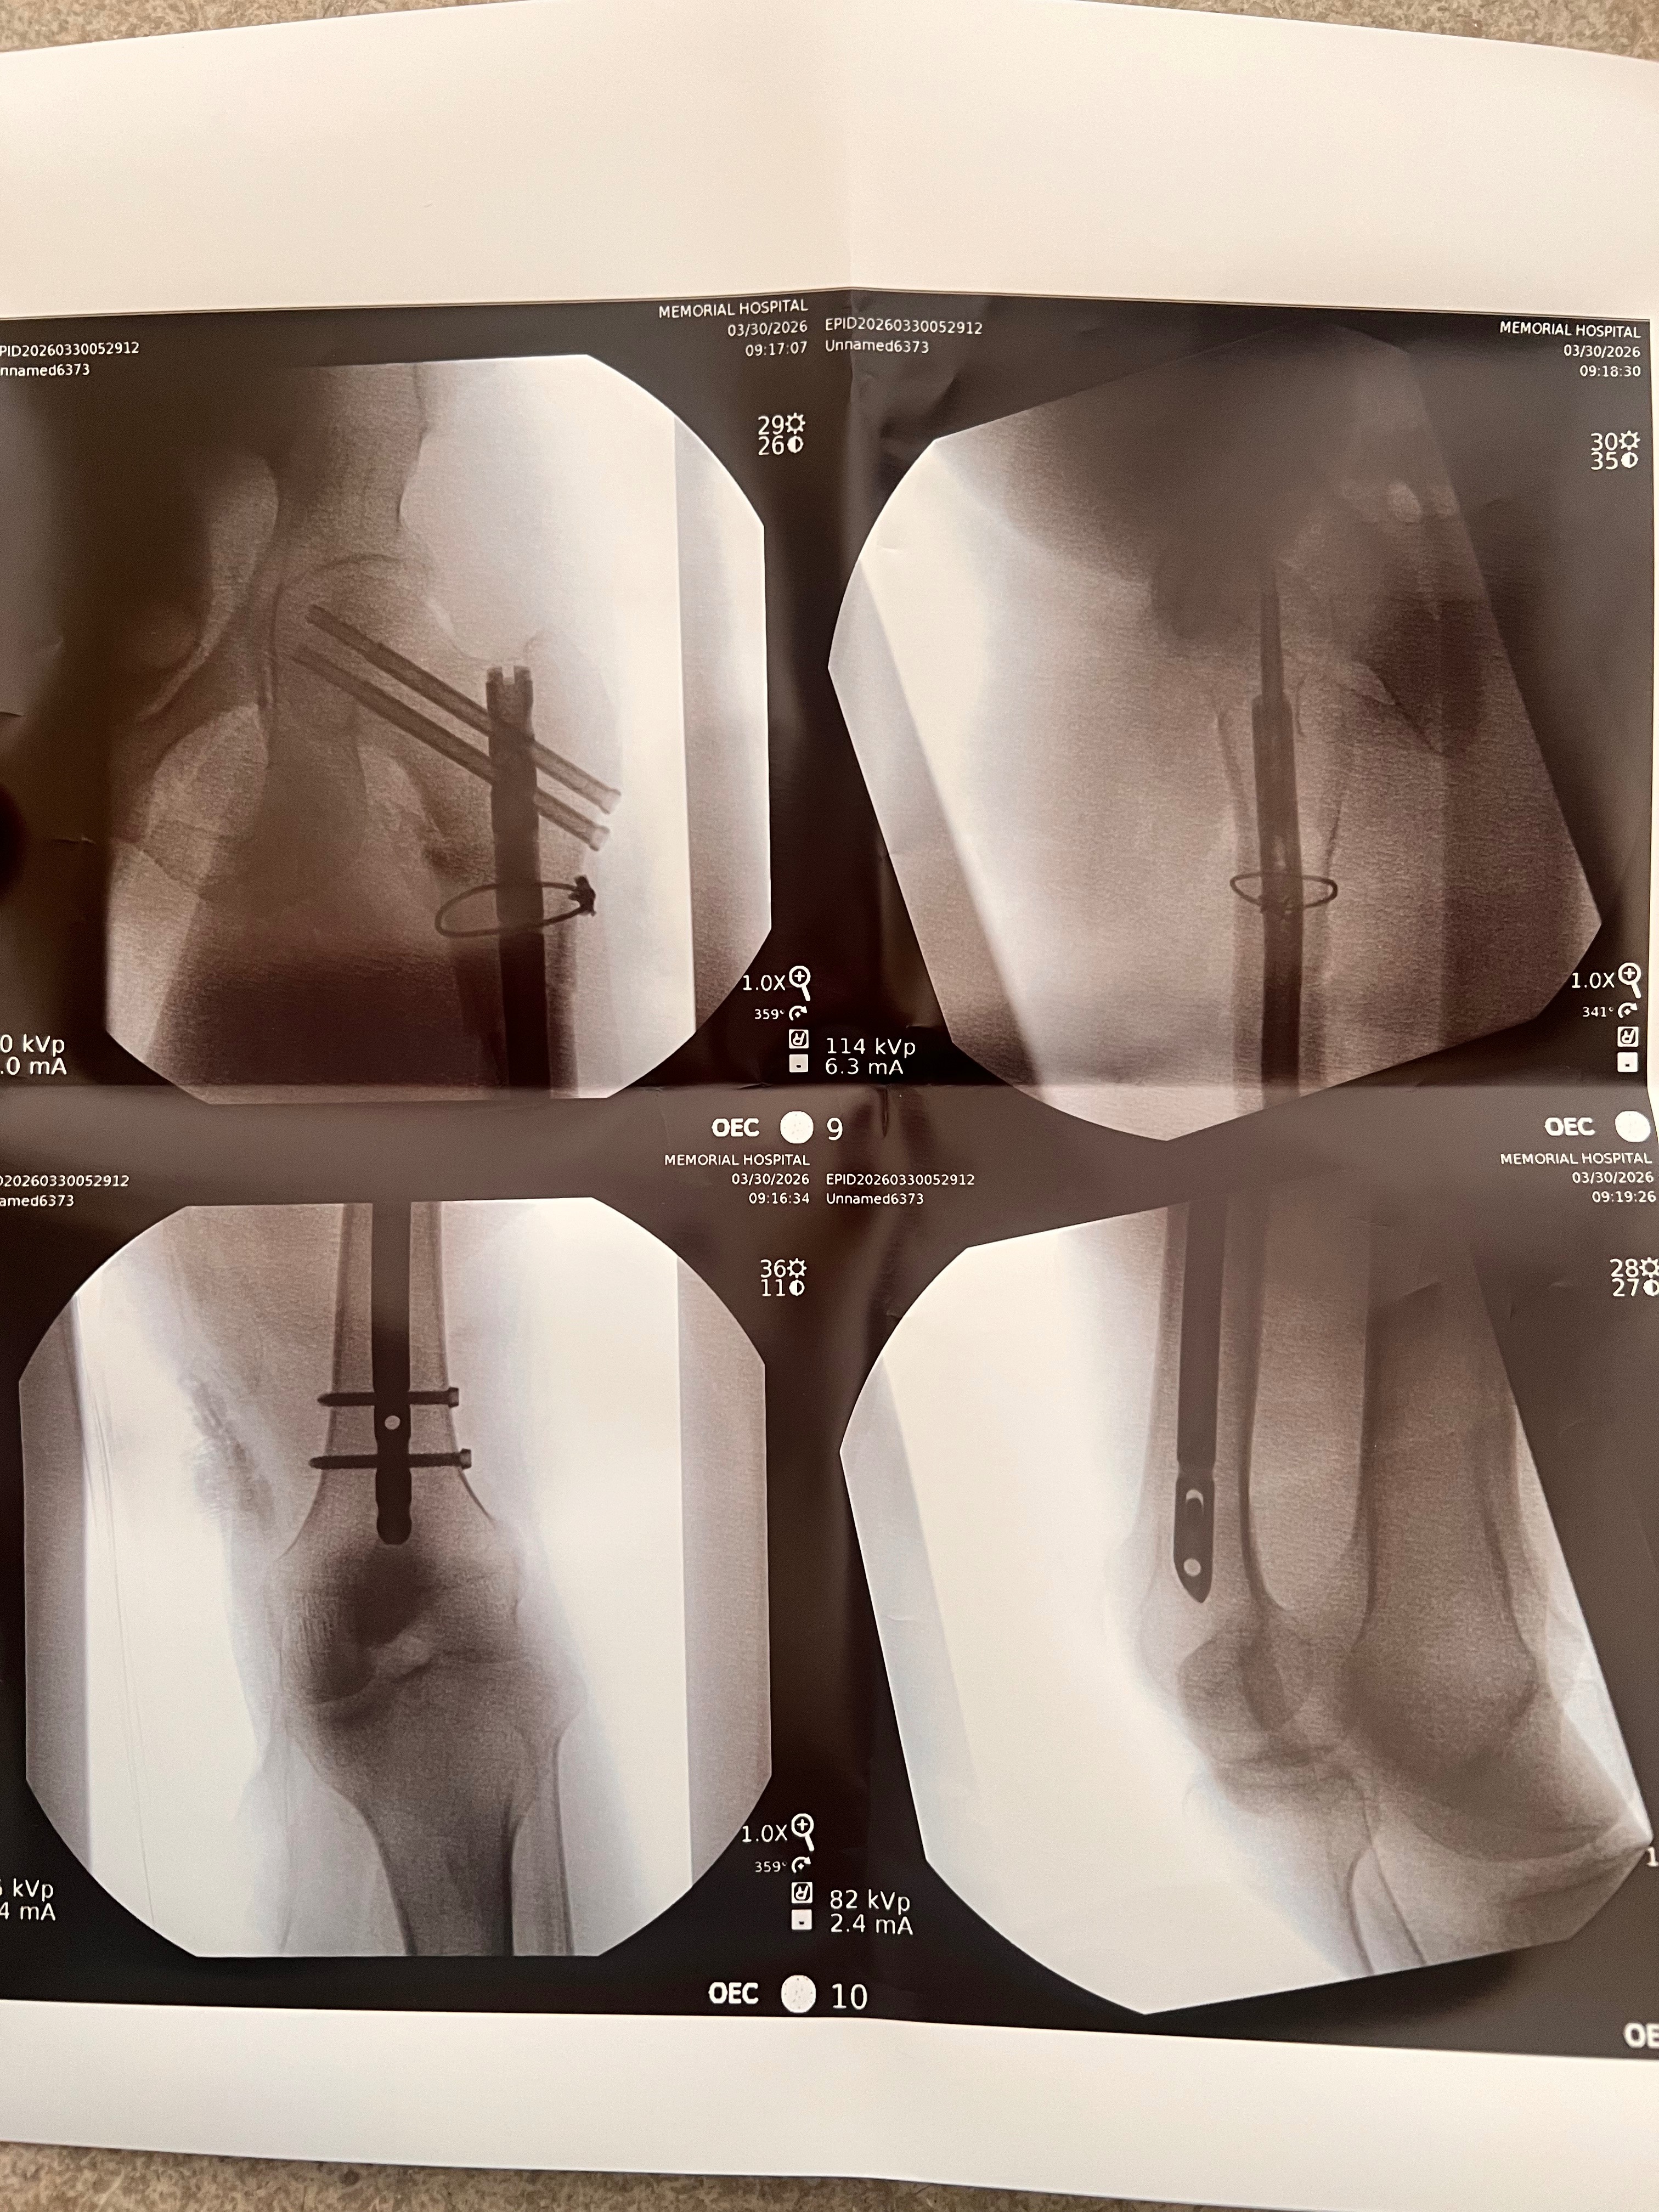

He successfully underwent surgery to insert a metal rod extending from his hip down to his knee to stabilize the injury.